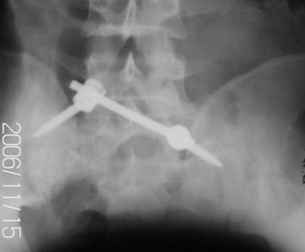

Застарелый перелом таза - результат

Уважаемые коллеги! 27 июля 2006г. представлял на форум больного со сложным застарелым переломом таза. Сейчас провели контрольное обследование.

Результат представляю в картинках.

Фиксация сзади выполнена системой "Силует" фирмы "Зиммер", предназначенной для транспедикулярной стабилизации позвоночника. Юрий Алексеевич Булахтин